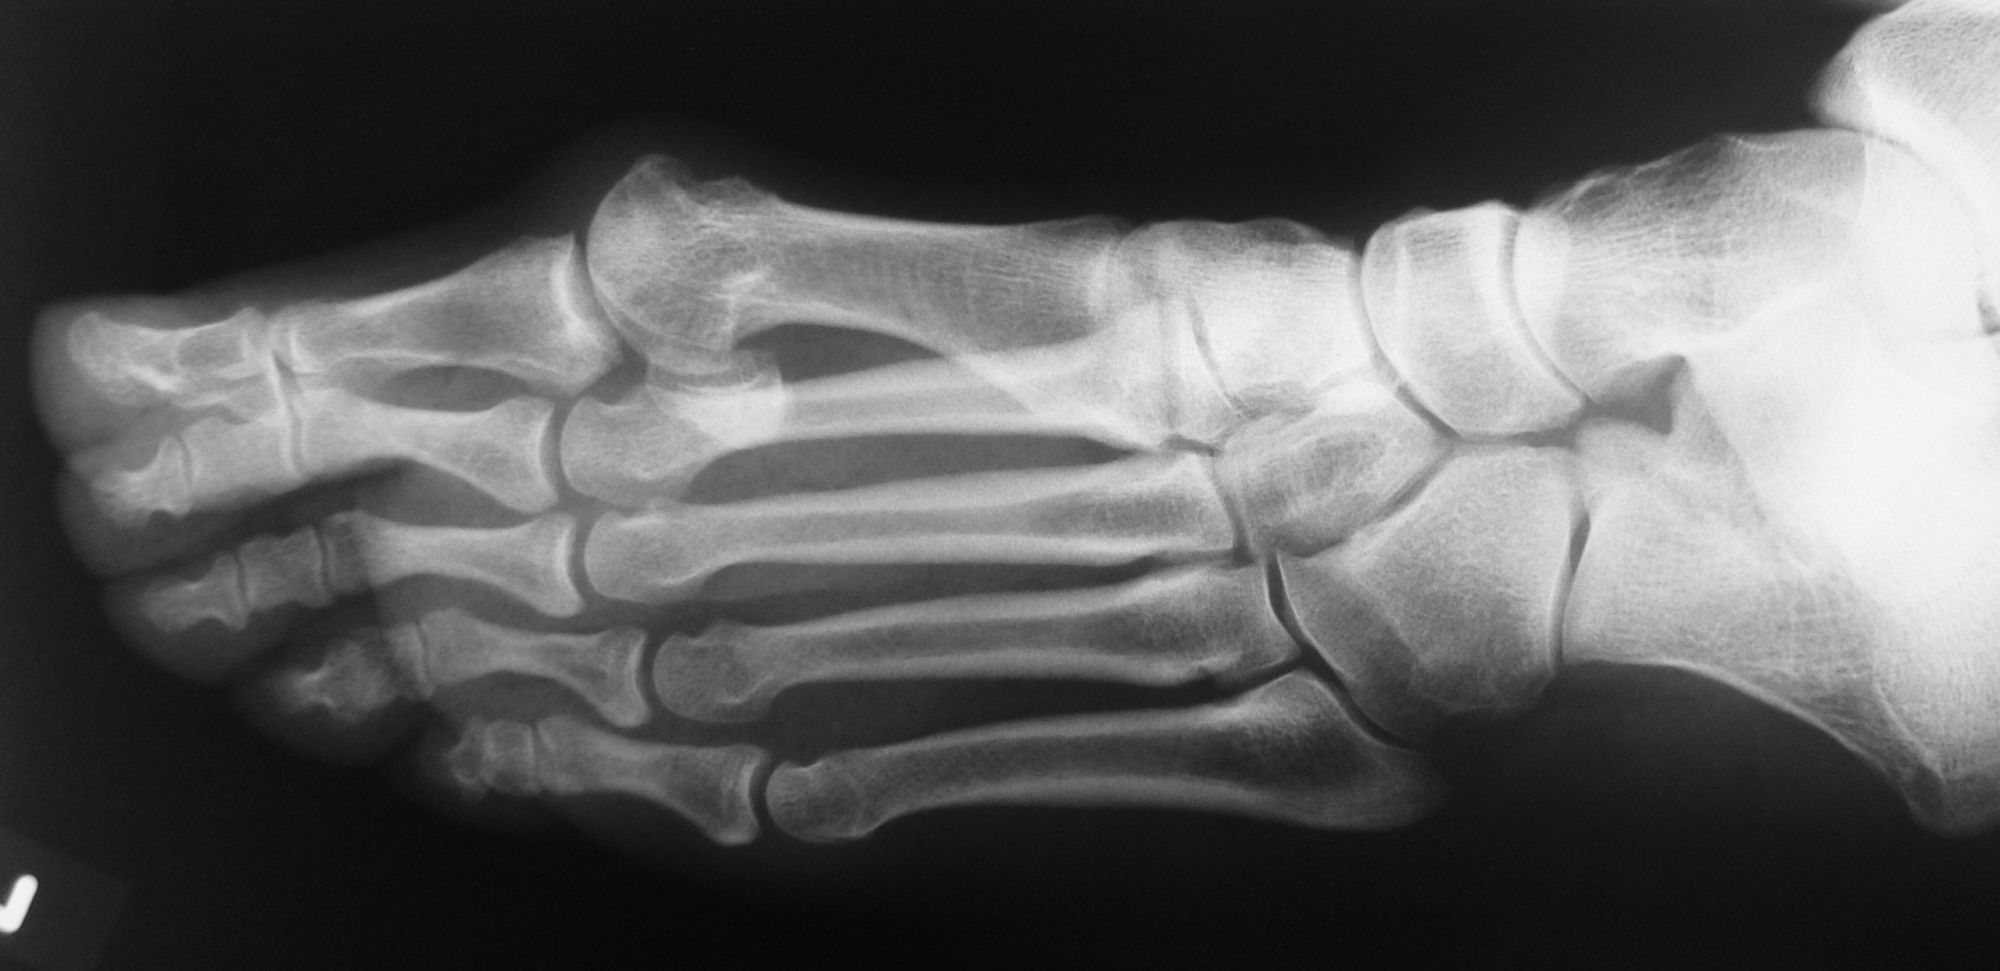

Röntgenaufnahme des Fußes (unter Belastung) in dorsoplantarem, seitlichen und schrägem Strahlengang (Abb. 1a-c).

Beurteilung des ersten Intermetatarsalwinkels (IMA), des Hallux valgus Winkels (HVA), des distalen (Distal Metatarsal Articular Angle, DMAA) und proximalen Gelenkflächenwinkels der Grundphalanx (Proximal Phalangeal Articular Angle, PPAA). Möglicherweise muss die Arthrodese des TMT-1-Gelenks mit weiteren distalen Eingriffen zur Korrektur des Gelenkwinkels kombiniert werden (z.B.: retrokapitale Osteotomie oder Grundphalanxosteotomie).

Zur Vollansicht bitte die Bilder anklicken.

Abbildung 1a

Abbildung 1b

Abbildung 1c